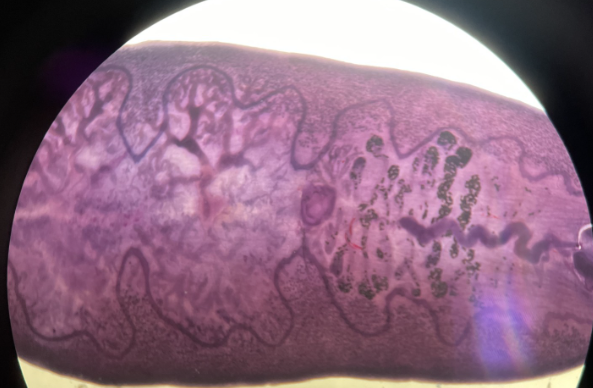

H&E stain of liver tissue

Schistosoma mansoni ova

Schistosoma mansoni ova